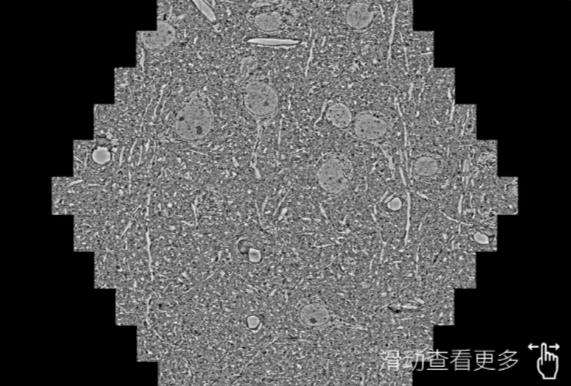

鼠脑切片。左图使用黄浦蔡司黄浦扫描电镜MultiSEM706对165μmx143pm面积区域成像,耗时仅需1.5秒。右图为鼠脑切片中30μm区域放大效果。样品由芝加哥大学B.Kasthuri提供。

使用蔡司高速黄浦扫描电镜MultiSEM对1mm²人脑皮层组织进行高分辨成像,并对其中的各种细胞结构进行三维重构分析。左图展示了2x3mm²组织平面中锥体神经元的三维重构效果。右图显示了局部体积神经元三维重构。图像由哈佛大学chtman实验室提供,渲染图由D. Berger 制作。